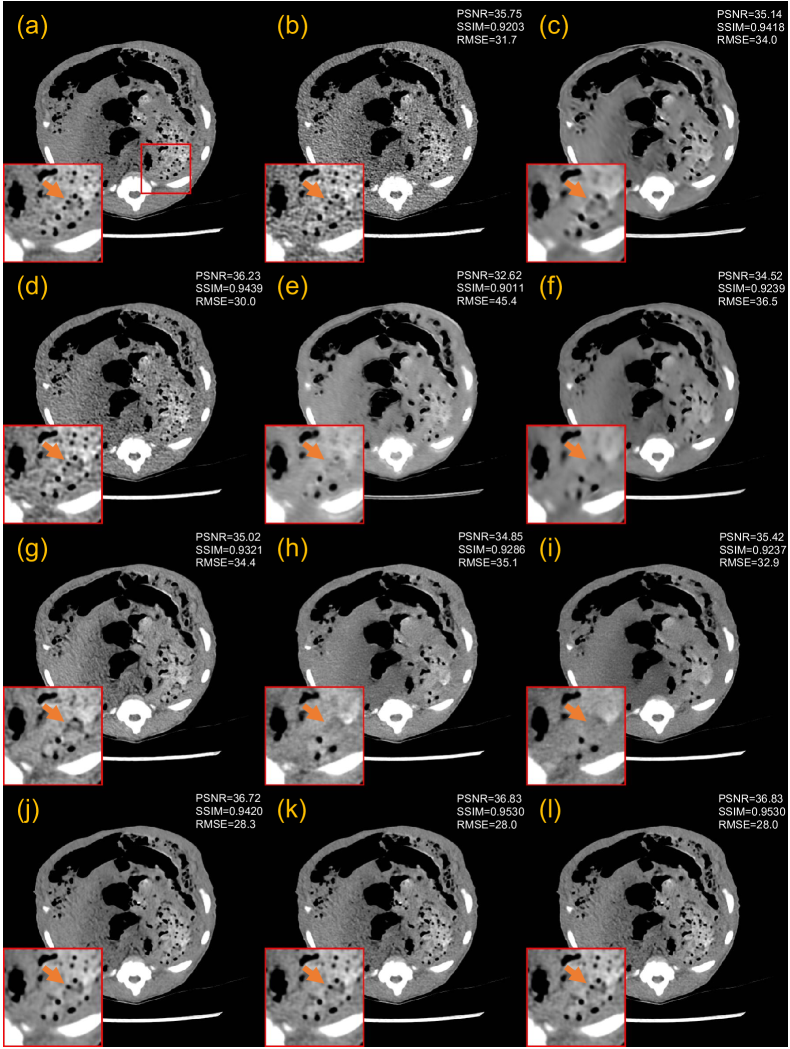

3.5.3 Generalization to the piglet dataset

We also examined the proposed one-shot framework in enhancing the generalization performance on the piglet dataset. We tested all the trained models on 25% and 10% doses of data from the piglet dataset. One slice is also selected from this piglet dataset with its (un)paired normal-dose slice to train our CoreDiff+OSLp, and CoreDiff+OSLu.

Figs. 12 and 13 show the denoising results of two representative slices of 25% and 10% doses. In the 10% dose scenario, RED-CNN, WGAN-VGG, and CNCL-U-Net severely blur the denoised image. While DU-GAN and IDDPM manage to avoid global smoothing, they still result in the loss of crucial local details. PDF-RED-CNN and CoreDiff successfully preserve fine details. When integrated with the OSL framework, the denoised images from CoreDiff+OSLp and CoreDiff+OSLu exhibit textures closest to the NDCT image. CoreDiff+OSLp and CoreDiff+OSLu also improve the quantitative performances over CoreDiff, and outperform other methods. In the 25% dose scenario, surprisingly, the quantitative metrics of the remaining methods except CoreDiff+OSLp and CoreDiff+OSLu are even worse than that of FBP. This observation highlights the limitations of DL-based models when generalizing across multi-center, multi-species CT data. However, the denoised images by CoreDiff+OSLp and CoreDiff+OSLu within our OSL framework consistently demonstrate superior visual quality and quantitative performance.